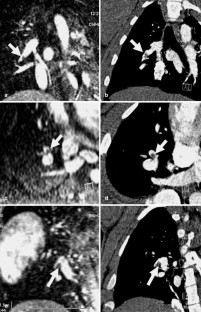

The purpose of this study was to assess the feasibility of contrast-enhanced 3D perfusion MRI and MR angiography (MRA) of pulmonary embolism (PE) in pigs using a single injection of the blood pool contrast Gadomer. PE was induced in five domestic pigs by injection of autologous blood thrombi. Contrast-enhanced first-pass 3D perfusion MRI (TE/TR/FA: 1.0 ms/2.2 ms/40°; voxel size: 1.3×2.5×4.0 mm3; TA: 1.8 s per data set) and high-resolution 3D MRA (TE/TR/FA: 1.4 ms/3.4 ms/40°; voxel size: 0.8×1.0×1.6 mm3) was performed during and after a single injection of 0.1 mmol/kg body weight of Gadomer. Image data were compared to pre-embolism Gd-DTPA-enhanced MRI and post-embolism thin-section multislice CT (n=2). SNR measurements were performed in the pulmonary arteries and lung. One animal died after induction of PE. In all other animals, perfusion MRI and MRA could be acquired after a single injection of Gadomer. At perfusion MRI, PE could be detected by typical wedge-shaped perfusion defects. While the visualization of central PE at MRA correlated well with the CT, peripheral PE were only visualized by CT. Gadomer achieved a higher peak SNR of the lungs compared to Gd-DTPA (21±8 vs. 13±3). Contrast-enhanced 3D perfusion MRI and MRA of PE can be combined using a single injection of the blood pool contrast agent Gadomer.

Fig. 4